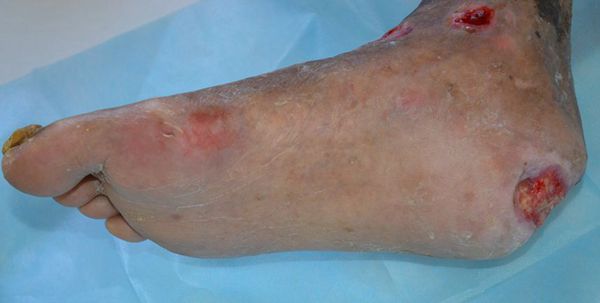

患者闫先铎,男,66岁。住院号:707574601  联系电话:15953470579  脑出血致瘫痪多年并糖尿病史10年余,继发右足压迫性溃疡(糖尿病足)3个月(图1 )。入院后右足清创,创面应用一途生肌育肤膏包扎疗法,第20天创面红润,肉芽新鲜(图2);继续用药,45天疮面愈合。

图1  糖尿病足